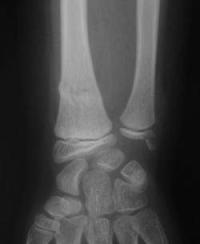

Fracture métaphysaire du poignet